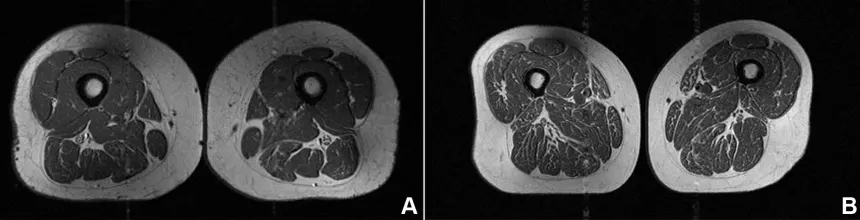

Η εικόνα που εξετάζουν οι ερευνητές δεν είναι ωστόσο φαγητό. Πρόκειται για μαγνητική τομογραφία (MRI) του μηρού μιας 62χρονης γυναίκας, η οποία αντλούσε το 87% των ετήσιων θερμίδων της από υπερεπεξεργασμένα τρόφιμα.

Στη μελέτη, μια δεύτερη γυναίκα 61 ετών εμφάνισε επίσης λιπώδη διήθηση στους μηρούς, αλλά σε μικρότερο βαθμό, με το 29% της διατροφής της να προέρχεται από υπερεπεξεργασμένα τρόφιμα.

Η γυναίκα με 87,1% υπερεπεξεργασμένα τρόφιμα στη διατροφή της (A στην εικόνα παρακάτω) είχε BMI 32,6 και χαμηλότερη φυσική δραστηριότητα από τη δεύτερη γυναίκα (B στην εικόνα), η οποία είχε BMI 31,8 και 29,5% υπερεπεξεργασμένα τρόφιμα. Παρ’ όλα αυτά, η πρώτη εμφάνιζε πολύ πιο έντονη λιπώδη διήθηση στους μηρούς.